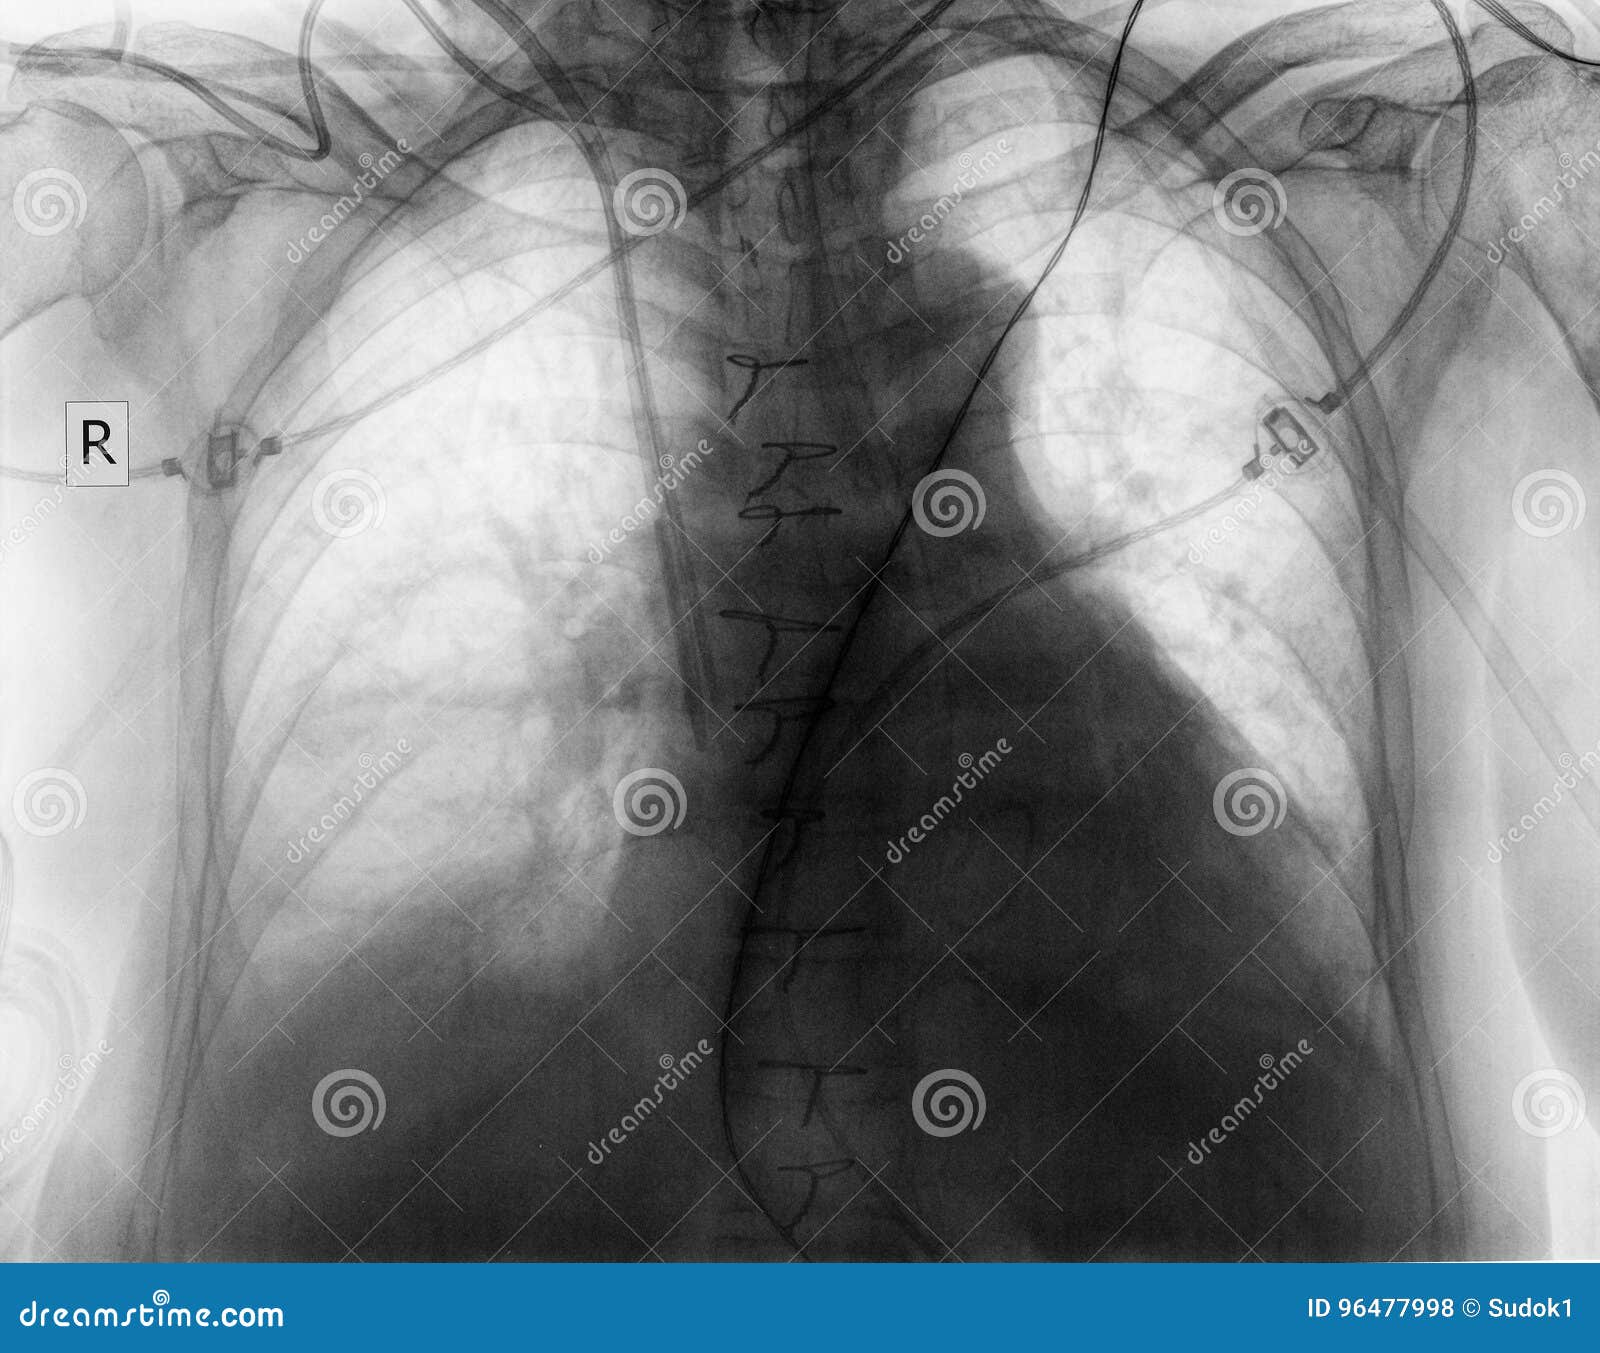

From www.dreamstime.com

Plain Chest Radiograph of Patient after Surgery Stock Photo Image of cardiac, pathology 96477998 Chest Pain After Surgery does it fully heal? At first, you’ll get your pain medication through your epidural catheter or iv. symptoms are chest pain, trouble breathing, coughing (may cough up blood), sweating, very low blood pressure, fast heartbeat,. You may feel muscle pain in the neck, shoulders, back or chest from lying on the operating table. you will have some. Chest Pain After Surgery.

From johnsonfrancis.org

Post CABG Xray chest PA view All About Cardiovascular System and Disorders Chest Pain After Surgery symptoms are chest pain, trouble breathing, coughing (may cough up blood), sweating, very low blood pressure, fast heartbeat,. you will have some pain after your thoracic surgery. To perform open heart surgery, a surgeon needs to cut through a person’s sternum in a. At first, you’ll get your pain medication through your epidural catheter or iv. You may. Chest Pain After Surgery.

From intensiveblog.com

A Chest Radiograph after Cardiac Surgery INTENSIVE Chest Pain After Surgery You may feel muscle pain in the neck, shoulders, back or chest from lying on the operating table. symptoms are chest pain, trouble breathing, coughing (may cough up blood), sweating, very low blood pressure, fast heartbeat,. To perform open heart surgery, a surgeon needs to cut through a person’s sternum in a. does it fully heal? you. Chest Pain After Surgery.